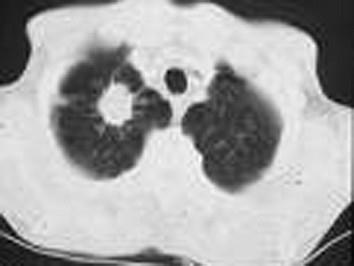

问题 男,60岁,右肩及右上肢持续疼痛2个月,需服用止痛药,无明显咳嗽,咯血,呼吸困难,检查右锁骨上未及淋巴结,颈静脉怒张,气管不偏移,右瞳孔缩小,眼睑下垂,右面部无汗,胸部CT如图所示,肋骨未见明显破坏,上纵隔淋巴结肿大1.5cm,临床诊断为Pancoast综合征。 根据TNM分期,应属于 ( )